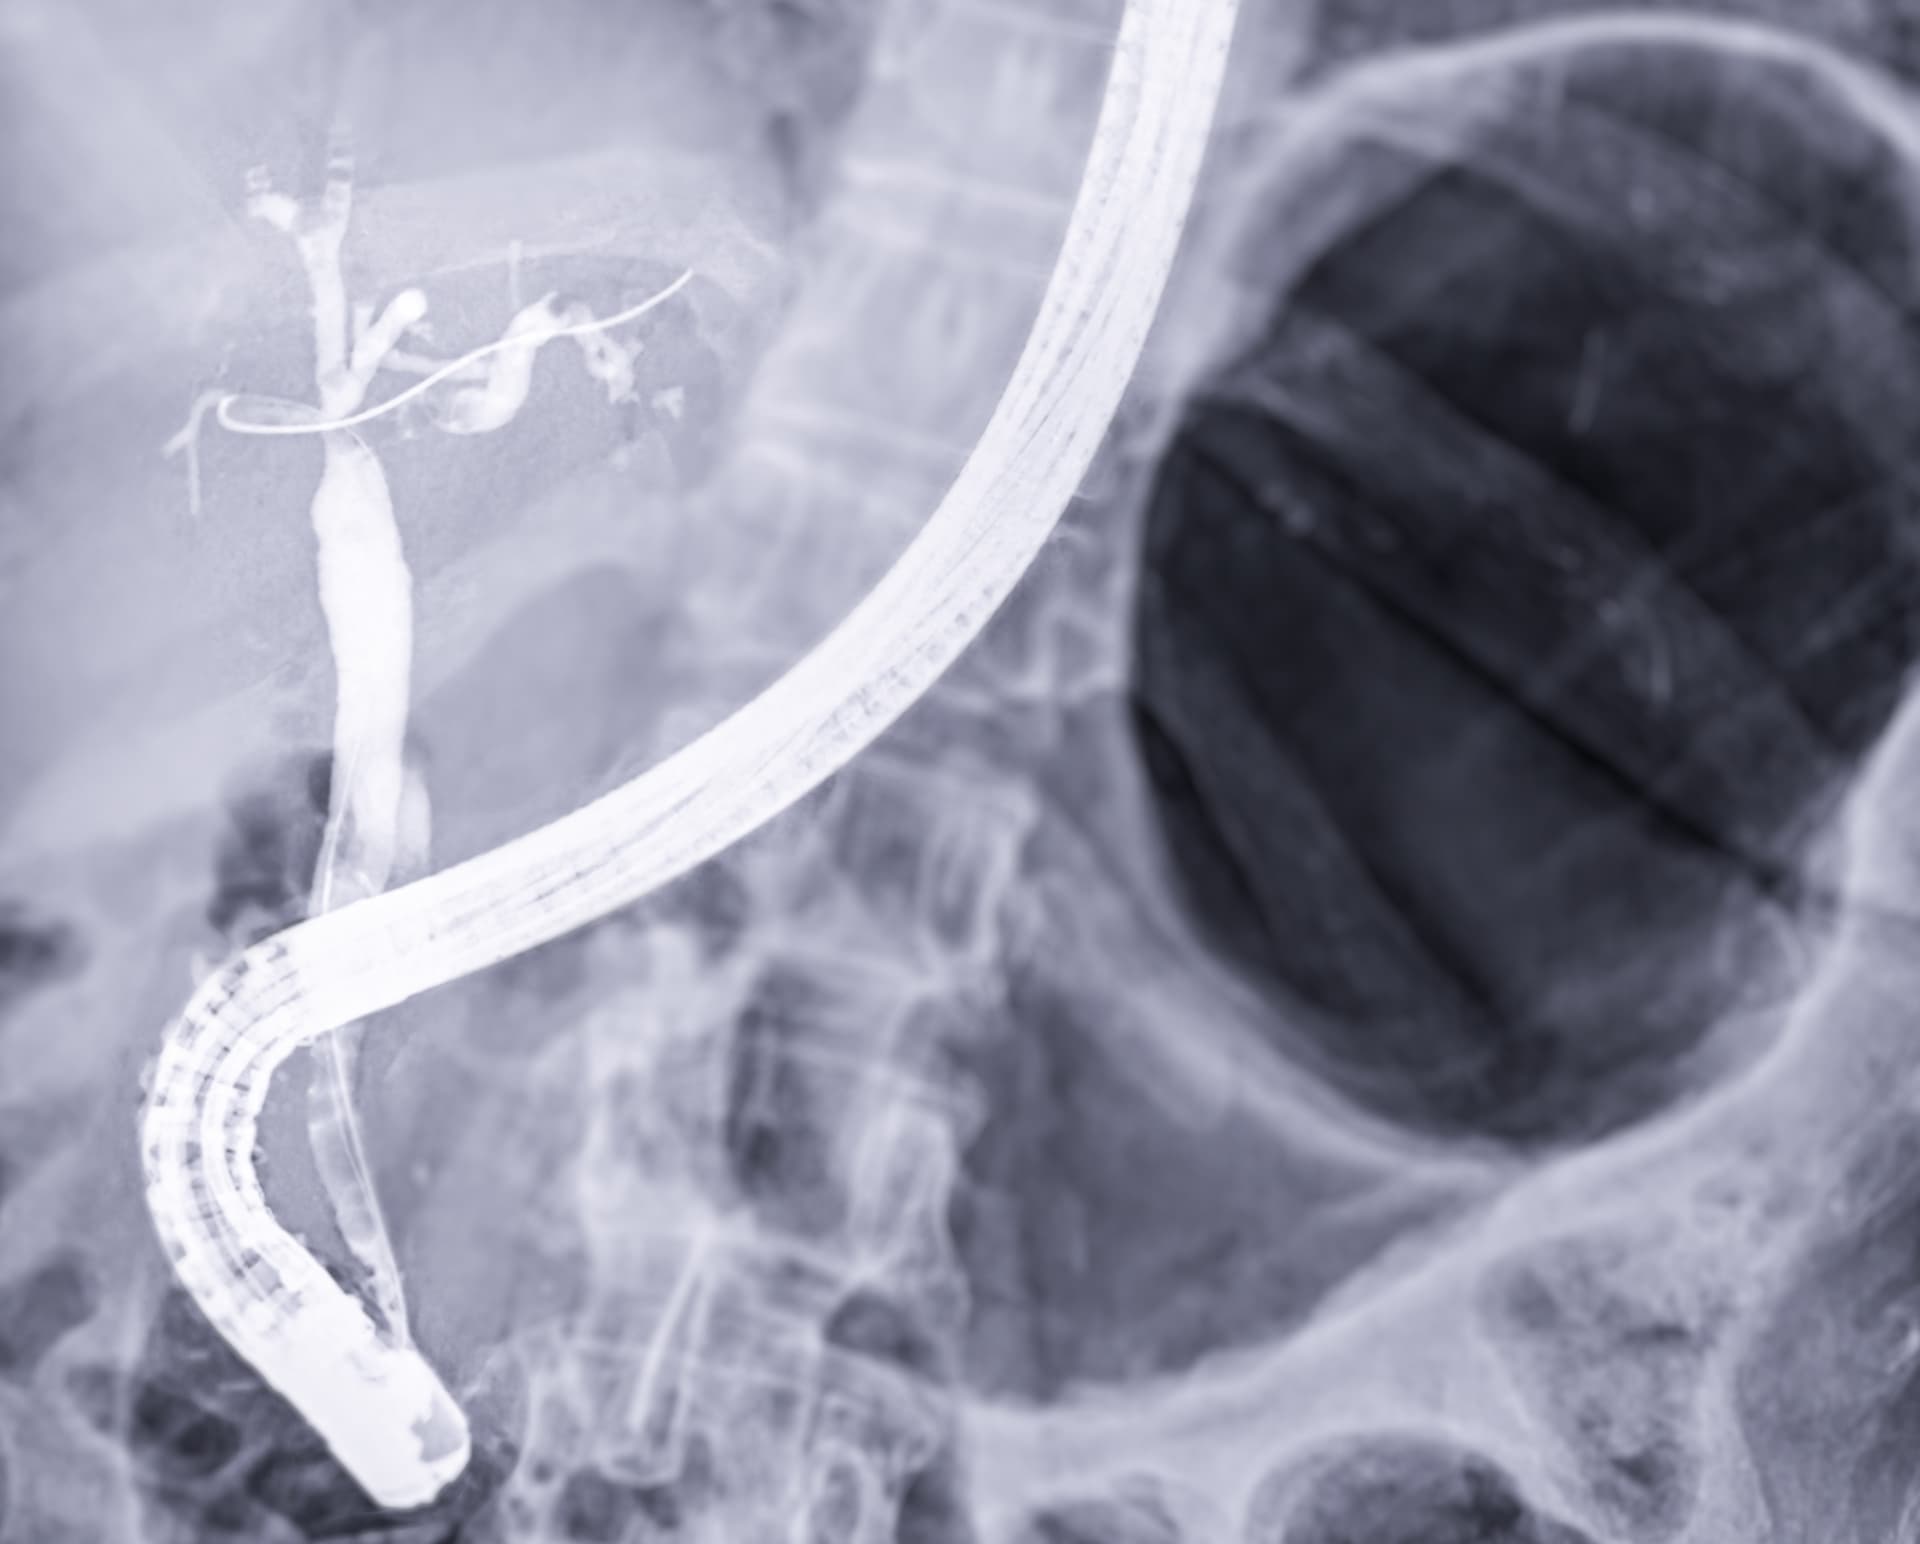

ERCP (Endoscopic Retrograde Cholangiopancreatography)

A specialised endoscopic procedure to inspect and treat blockages of the bile duct. Stones can be treated by removing them or placing a small tube (stent) to keep the duct open.

Learn more about this procedure →